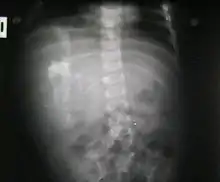

Fetus in fetu (or foetus in foetu) is a developmental abnormality in which a mass of tissue resembling a fetus forms inside the body. An early example of the phenomenon was described in 1808 by George William Young.[1]

There are two theories of origin concerning "fetus in fetu". One theory is that the mass begins as a normal fetus but becomes enveloped inside its twin.[2] The other theory is that the mass is a highly developed teratoma. "Fetus in fetu" is estimated to occur in 1 in 500,000 live births.[3]

Fetus in fetu may be a parasitic twin fetus growing within its host twin. Very early in a monozygotic twin pregnancy, in which both fetuses share a common placenta, one fetus wraps around and envelops the other. The enveloped twin becomes a parasite, in that its survival depends on the survival of the host twin, by drawing on the host twin's blood supply. The parasitic twin is anencephalic (without a brain) and lacks some internal organs, and as such is unable to survive on its own. As the host twin has to "feed" the enveloped twin from the nutrients received over a single umbilical cord, they usually die before birth.